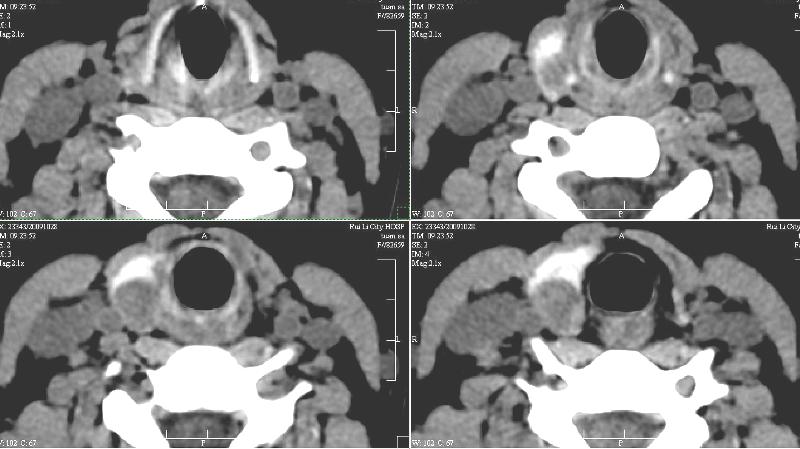

标题: CT23079:F,18.颈部包块3年。

ct:双侧多发性甲状腺占位,考虑多发性甲状腺腺瘤伴部分腺瘤内出血可能大。

结节性甲状腺肿并囊变。